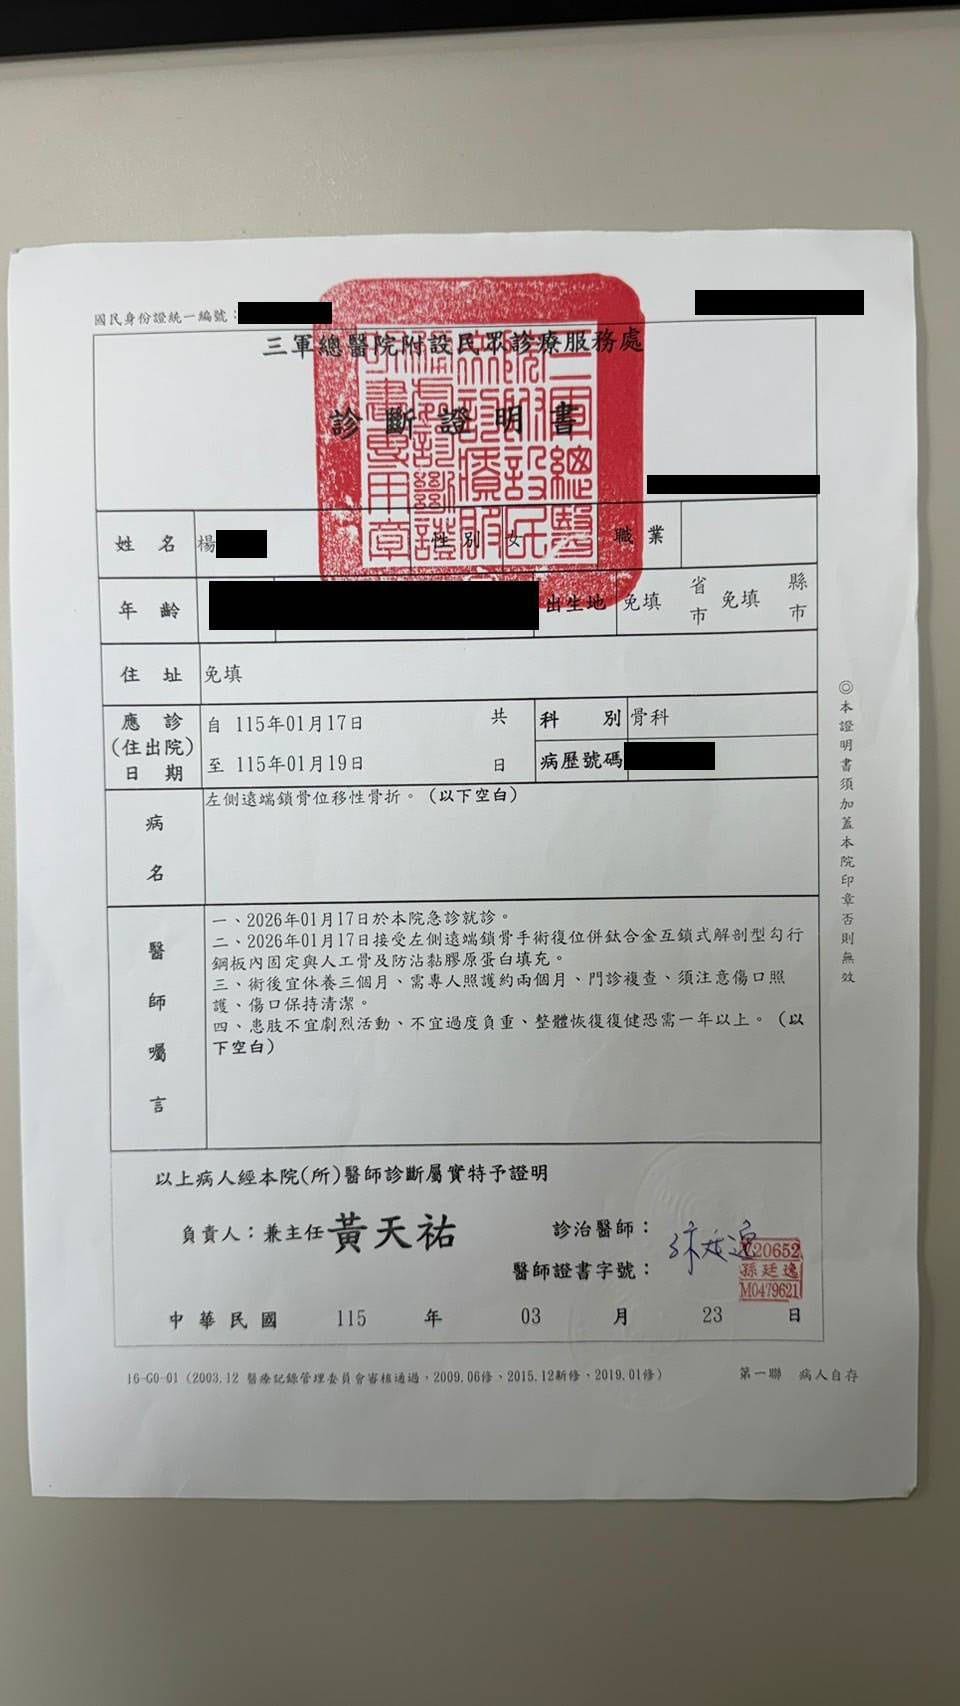

往下了解事件全貌 ↓民國 115 年 1 月 17 日,原告Doris參加東三塔自行車活動時,被告翁先生從後方切入車道,未保持安全距離,後輪撞上原告前輪,導致原告摔車,造成左側鎖骨骨折,緊急手術植入鈦金屬骨板,醫囑恢復需一年以上。

左側遠端鎖骨位移性骨折,手術植入鈦金屬骨板,恢復需一年以上

另依診斷證明書醫囑「需專人照護約兩個月」,看護費以每日 $2,200 計算共 $132,000。

看護費依三軍總醫院診斷證明書醫囑「需專人照護約兩個月」計算。車損尚未列入。

東三塔自行車挑戰活動,台2線 32.3K。原告左側鎖骨骨折,緊急手術植入鈦骨板。